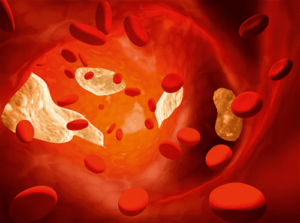

Jenis pertama diwakili oleh lipoprotein densitas tinggi, yang mencegah kontaminasi pembuluh darah dengan endapan asing. “Kolesterol jahat” mengacu pada lipoprotein densitas rendah yang dapat mengendap di dasar pembuluh darah dan menimbulkan masalah kesehatan.

Ada juga berbagai lipoprotein densitas sangat rendah. Peningkatan kolesterol jahat dalam darah, apa artinya? Setelah terbentuk, plak tidak hilang dari tubuh di mana pun. Dengan menyumbat arteri, itu mencegah lewatnya darah dan oksigen ke organ dalam.

Secara bertahap, lumen pembuluh menyempit, aterosklerosis sering didiagnosis pada usia muda.